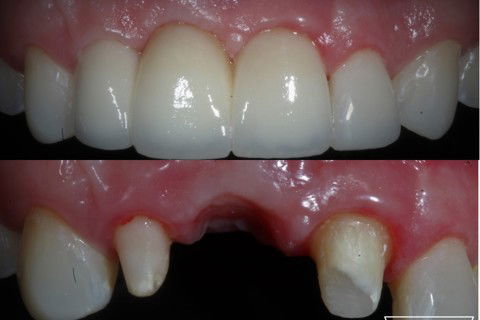

Resultado final, evidenciando a formação das papilas .

Resultados após condicionamento gengival

Resultado final após cimentação da ponte fixa em zircônia

Resultado imediato após cimentação do trabalho protético.

Ensaio fotográfico após finalização do caso.